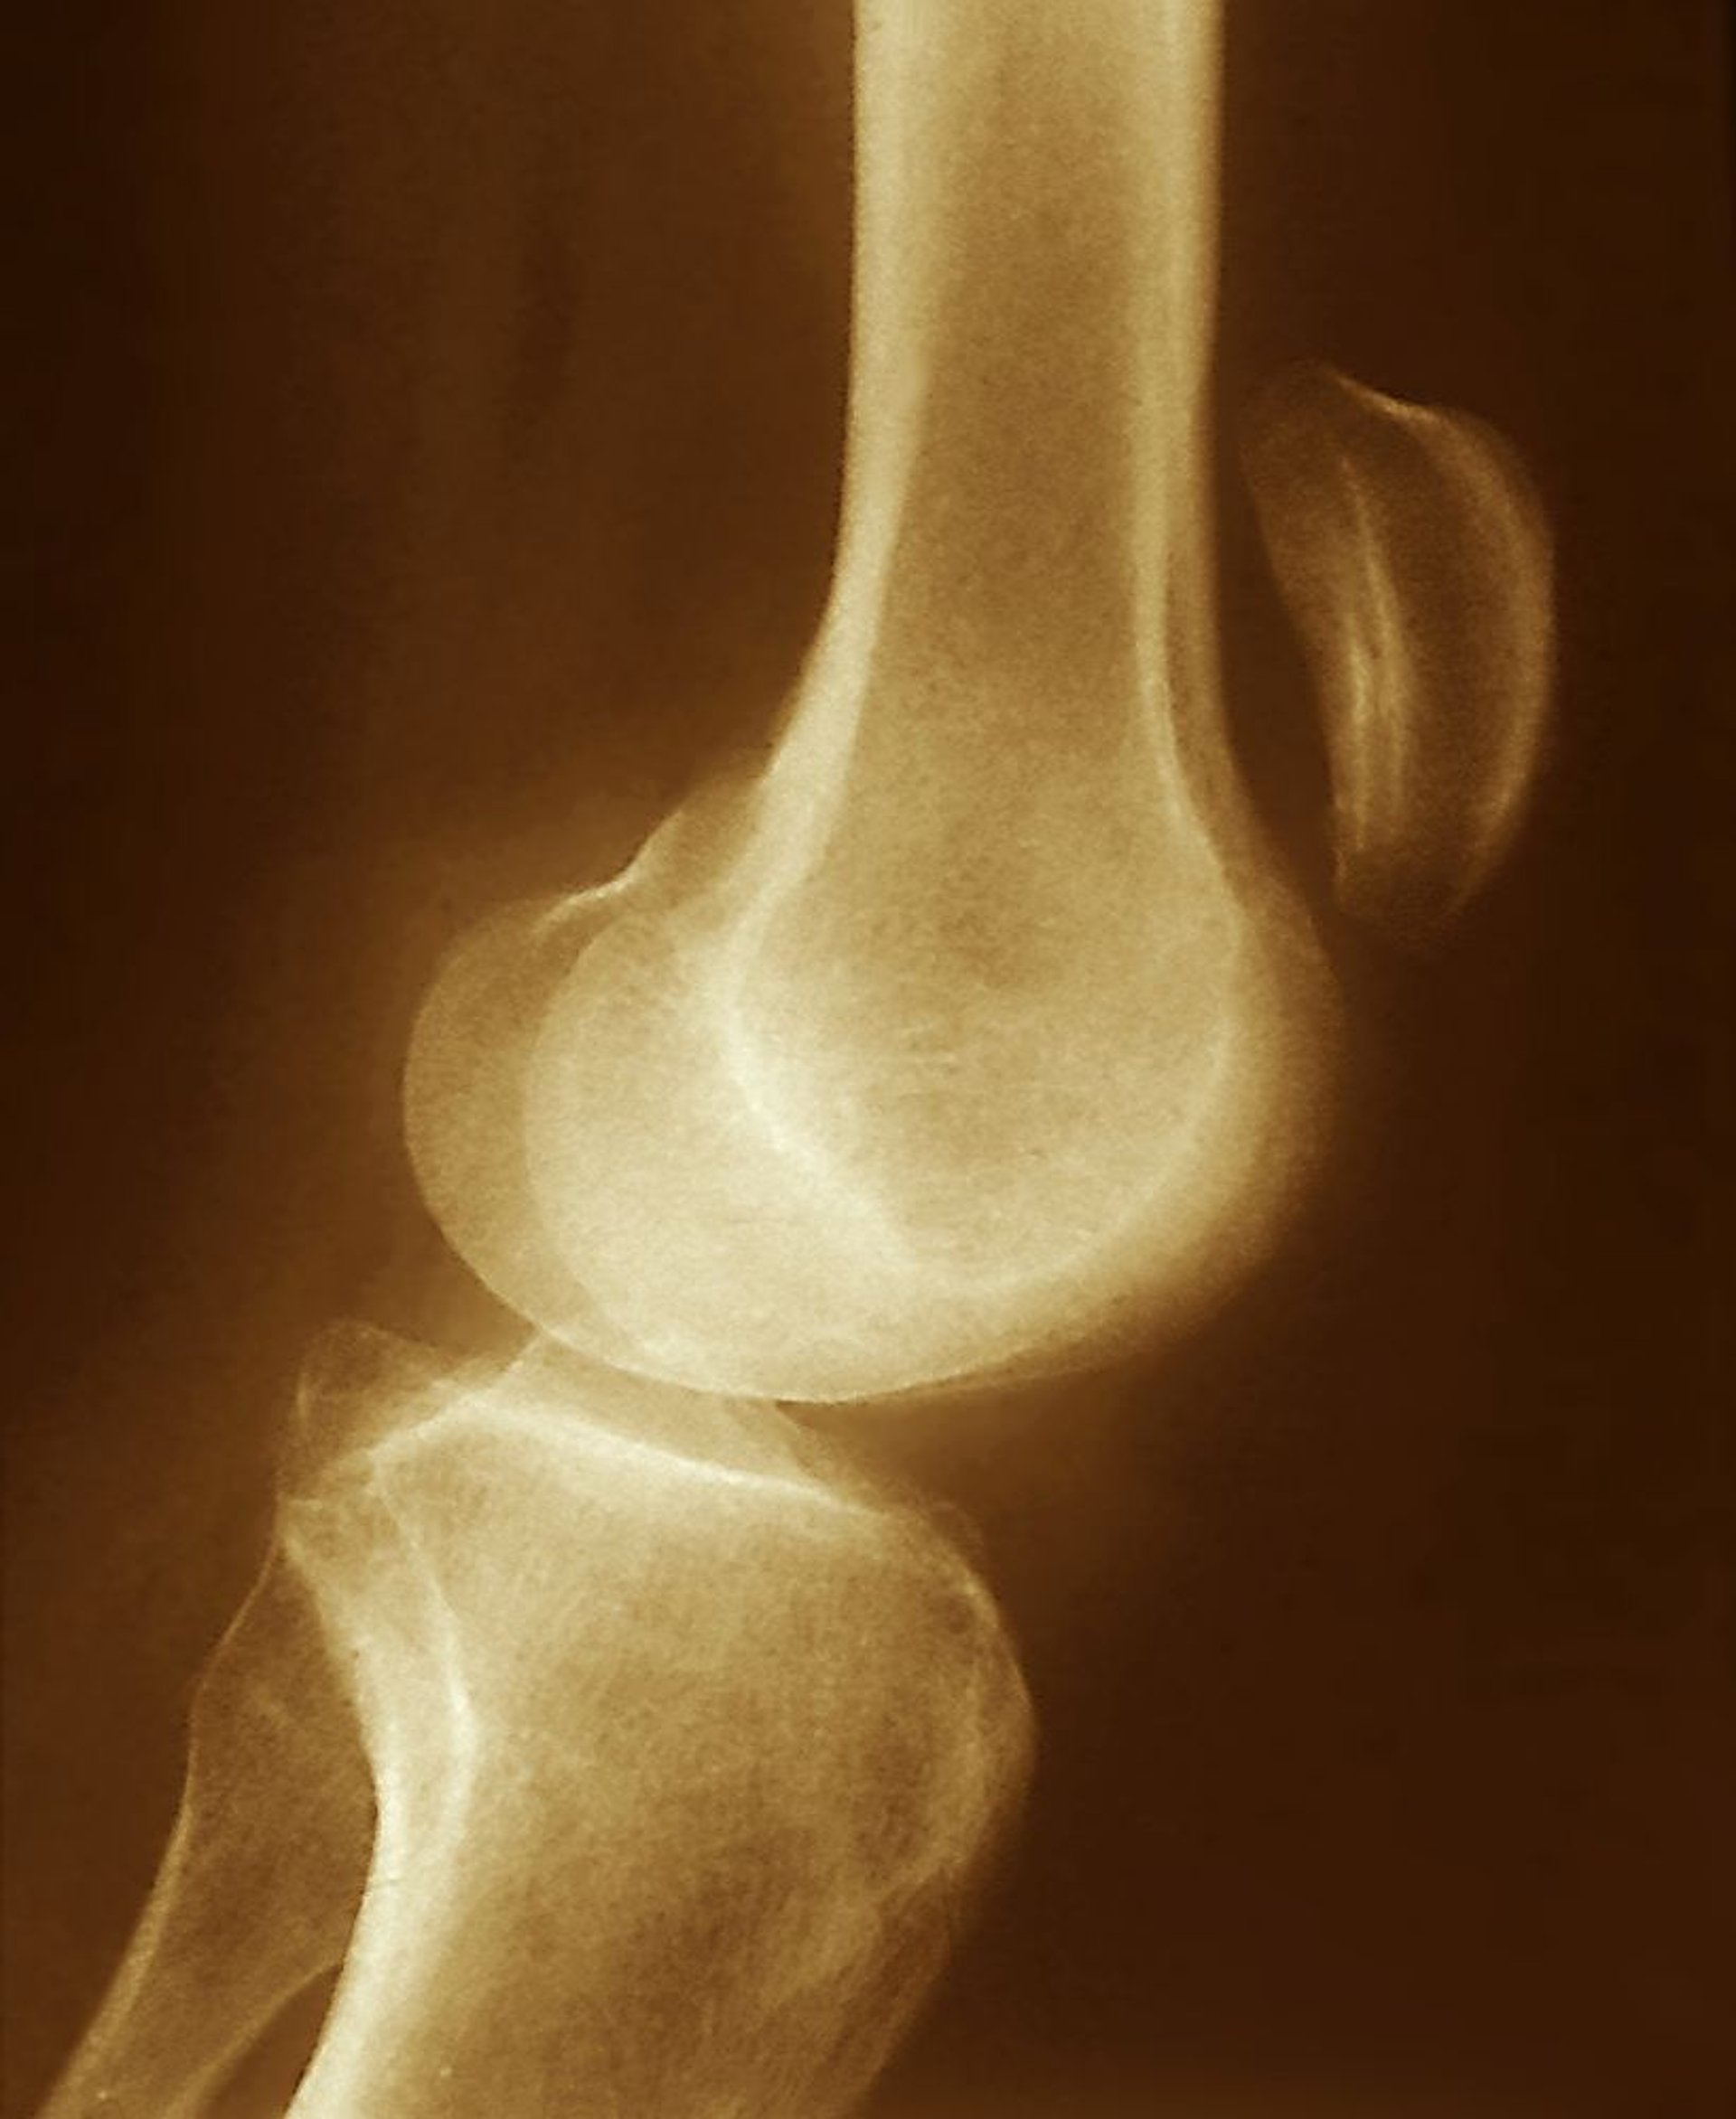

Lacerazione del tendine rotuleo

Lo spostamento superiore della rotula osservato su questa radiografia (ben al di sopra dell'articolazione del ginocchio) suggerisce una lesione del tendine rotuleo, con contrazione senza resistenza del muscolo quadricipite.